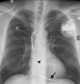

Pacemaker insertion

A cardiac pacemaker (or artificial pacemaker, so as not to be confused with the natural pacemaker of the heart), is a medical device that generates electrical impulses delivered by electrodes to cause the heart muscle chambers (the upper, or atria and/or the lower, or ventricles) to contract and therefore pump blood; by doing so this device replaces and/or regulates the function of the electrical conduction system of the heart. The primary purpose of a pacemaker is to maintain an adequate heart rate, either because the heart's natural pacemaker is not fast enough, or because there is a block in the heart's electrical conduction system. [Source: Wikipedia ]